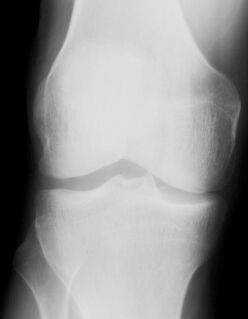

СНИМКИ КОЛЕННОГО СУСТАВА В ПРЯМОЙ ПРОЕКЦИИ

1. Чаще всего рентгенографию коленного сустава производят в прямой задней проекции. При этом больной лежит на спине, обе ноги вытянуты, сагиттальная плоскость стоп расположена перпендикулярно к плоскости стола. Кассету размером 18 х 24 см располагают в продольном положении. Проекция суставной щели, находящаяся при вытянутой ноге на 1,5—2 см ниже нижнего полюса надколенника, легко прощупываемого под кожей, соответствует средней линии кассеты. Пучок рентгеновского излучения направляют отвесно на центр кассеты (рис. 411).

Информативность снимка. На снимке коленного сустава в прямой задней проекции определяются дистальный метаэпифиз бедренной кости, медиальный и латеральный мыщелки бедра, между которыми располагается межмыщелковая ямка. Выше мыщелков определяются медиаль-ный и латеральный надмыщелки. На фоне дистального метаэпифиза бедренной кости виден надколенник. Проксимальный эпифиз большеберцовой кости представлен медиальным и латеральным мыщелками, между

которыми определяются медиальный и латеральный межмыщелковые бугорки. На латеральный отдел метаэпифиза большеберцовой кости частично накладывается головка малоберцовой кости. Между мыщелками бедренной и большеберцовой костей выявляется рентгеновская суставная щель коленного сустава в виде неравномерно изогнутой полосы просветления (рис. 415).

Информативность снимков коленного сустава как в задней прямой, так и в передней прямой проекциях одинаковая. В передней прямой проекции несколько лучше видна структура надколенника. Информативность одномоментных снимков коленных суставов в прямой задней проекции ниже, так как каждый из суставов при этом подвергается проекционным искажениям.